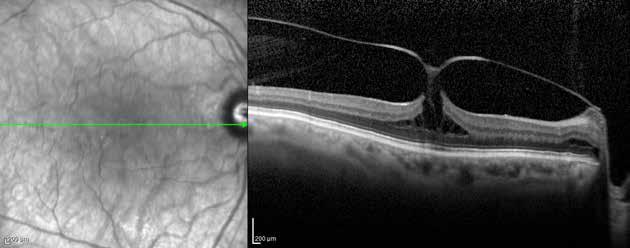

Type 1 MNV is characterized by the growth of vessels from the choriocapillaris into the subRPE space. On fluorescein angiography (FA), Type 1 MNV commonly presents late leakage of undetermined source, defined as areas of leakage at the level of the retinal pigment epithelium in the late phase of the angiogram without well-demarcated areas of hyperfluorescence in the early phase of the angiogram that would explain the leakage. It may also appear as fibrovascular pigment epithelial detachment, defined as areas of irregular retinal pigment epithelium elevation detectable on stereoscopic angiography. As a result, Type 1 MNV was originally termed occult neovascularization.3 Indocyanine green angiography (ICGA) should be used to visualize part of the vascular structure but it often reveals only late staining of the lesion, referred to as a plaque.4 (Figure 1)

1. Multimodal imaging of Type 1 macular neovascularization. Fundus autofluorescence (A) showing fine alteration of retinal pigment epithelium. Late phase (B) of fluorescein angiography revealing pinpoints of hyperfluorescence. Both early (C) and late phases (D) of indocyanine green angiography reveal a central hyperfluorescent zone, indicative of type 1 macular neovascularization, consistent with optical coherence tomography angiography (E). Optical coherence tomography displaying a shallow irregular elevation of retinal pigment epithelium (F).